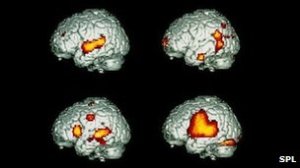

When we identify a person’s brain activity while that person is hearing or thinking about, for instance, the word jazz, we might see something like this: